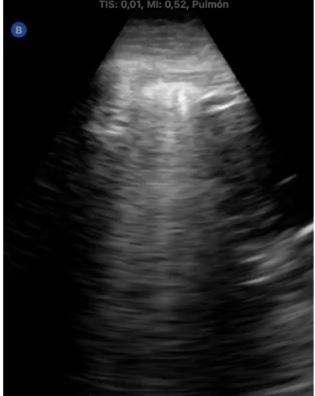

Presentamos tres casos consecutivos de pacientes con cáncer de mama que acudieron a consulta por tos seca persistente, disnea leve o febrícula con antecedente común de tratamiento con radioterapia. Se realizó ecografía pulmonar identificando líneas B focales en campos pulmonares irradiados y engrosamiento e irregularidad pleural, la más llamativa con consolidación, sin derrames.

Ante la duda diagnóstica, en dos casos se inició tratamiento antibiótico empírico y se repitió ecografía a los 7 días, sin cambios clínicos ni ecográficos, apoyando la sospecha de neumonitis rádica no infecciosa. Posteriormente, en las tomografías computerizadas de control oncológico realizadas semanas después, nuestros hallazgos fueron confirmados.